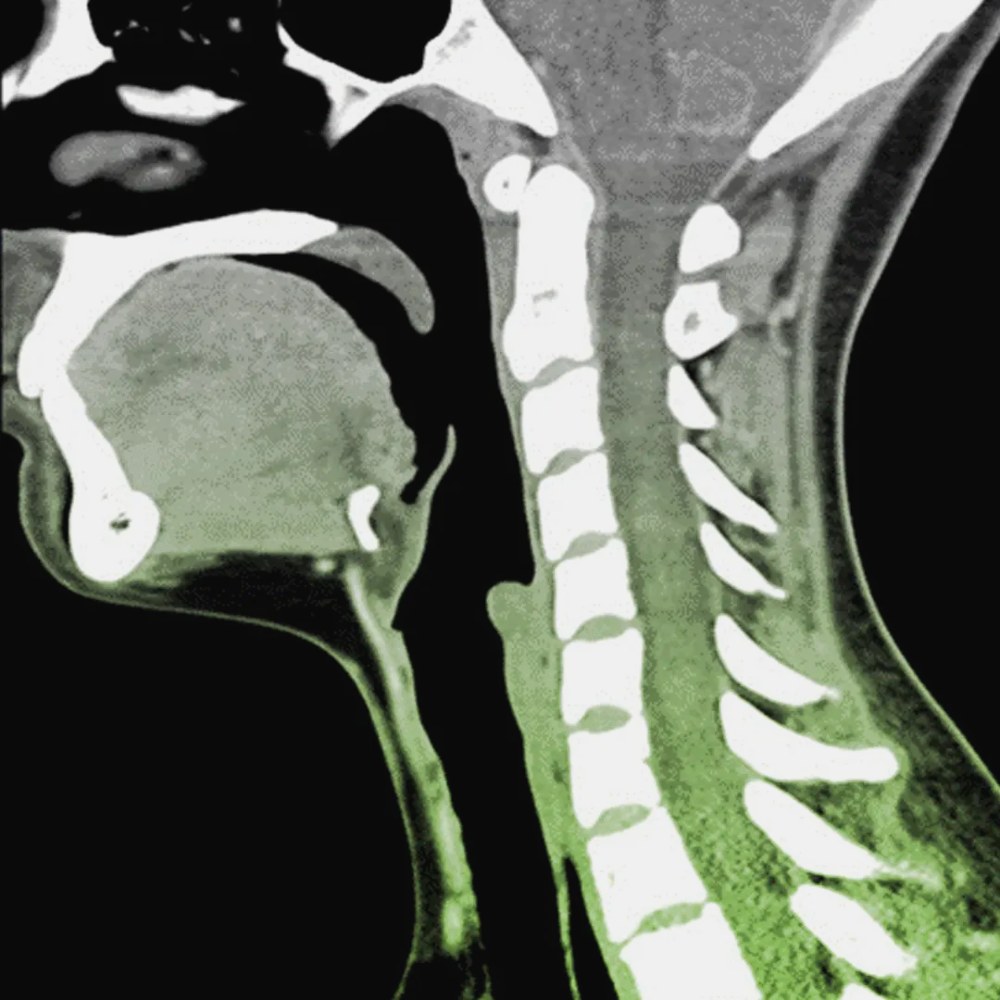

Комп’ютерна томографія шиї – один із найточніших діагностичних методів для оцінки стану кісткових структур, суглобів і нервових каналів у верхній частині хребта. КТ шийного відділу хребта дозволяє лікарю побачити пошарові знімки шийних хребців і навколишніх тканин, що дає детальне уявлення про стан пацієнта при підозрі на складні патології. Такий вид обстеження є результативним при виявленні причин болю в шиї та обмеження рухів, що робить його важливою частиною клінічної практики для постановки діагнозу та подальшого лікування.

Дане обстеження ефективне при підозрі на дегенеративно‑дистрофічні зміни міжхребцевих дисків, протрузії та грижі, що здавлюють нервові корінці чи судини, а також при станах, що супроводжуються болем у шиї, онімінням рук, поколюванням або слабкістю. КТ дозволяє оцінити анатомічні особливості будови шийного відділу, виявити вроджені аномалії або зміни, спричинені остеопорозом чи іншими метаболічними захворюваннями кісток.

Комп’ютерна томографія має високу роздільну здатність для оцінки кісткових структур і дозволяє виявляти пошкодження та патології, що непомітні на звичайних рентгенівських знімках. Вона менш чутлива до руху під час обстеження, а пацієнти з імплантованими електронними чи металевими пристроями можуть пройти дослідження без значних обмежень у порівнянні з магнітно‑резонансною томографією.